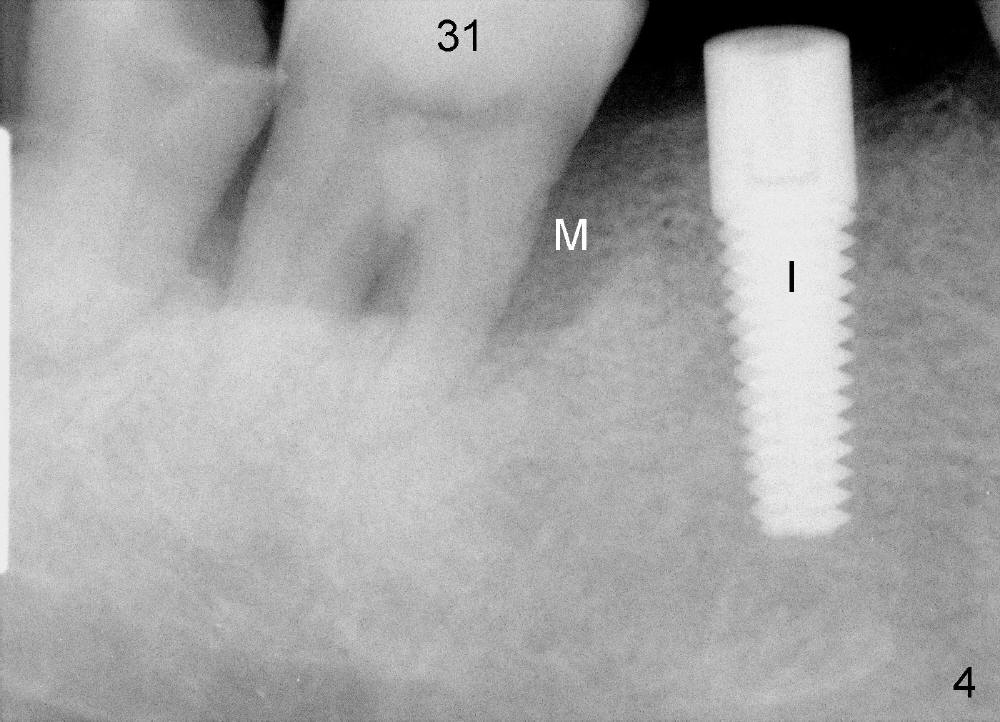

The tooth #31 of a 41-year-old man appears to have combined periodontitis and occlusal trauma: severe mesial bone resorption (Fig.1 (CT sagittal section),Fig.4 (PA)). In fact, the tooth #32 was extracted when a 5x17 mm implant was placed at the site of #30 (Fig.4).

CT coronal sections at the mesial root of #31 show that a 7x17 (Fig.2) or 7x14 mm (Fig.3) implant does not look too large for the alveolar bone buccolingually. The large implant is able to help close the large socket (mesial (Fig.1,4) and buccal (Fig.2,3) aspects), reducing the amount of bone graft (red circles) placed. In contrast, the buccolingual width of #30 is narrower (Fig.9 CT coronal section), allowing a smaller implant (6x17 mm by design (Fig.9), 5x17 mm clinically (Fig.4)).